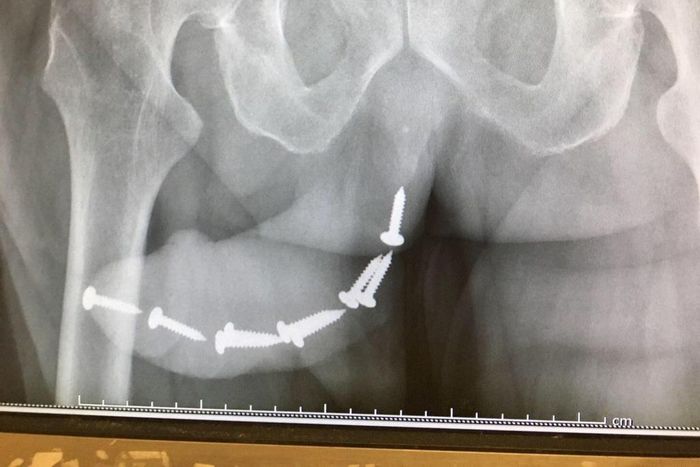

According to a post on Reddit, a young man had nine screws shoved up his urethra by his psycho estranged ex.

A photo shared on the social medium,

The story behind the scary x-ray photo?

A man allegedly passed out after being plied with alcohol by his estranged fuming ex-girlfriend and had nine screws shoved up his urethra.